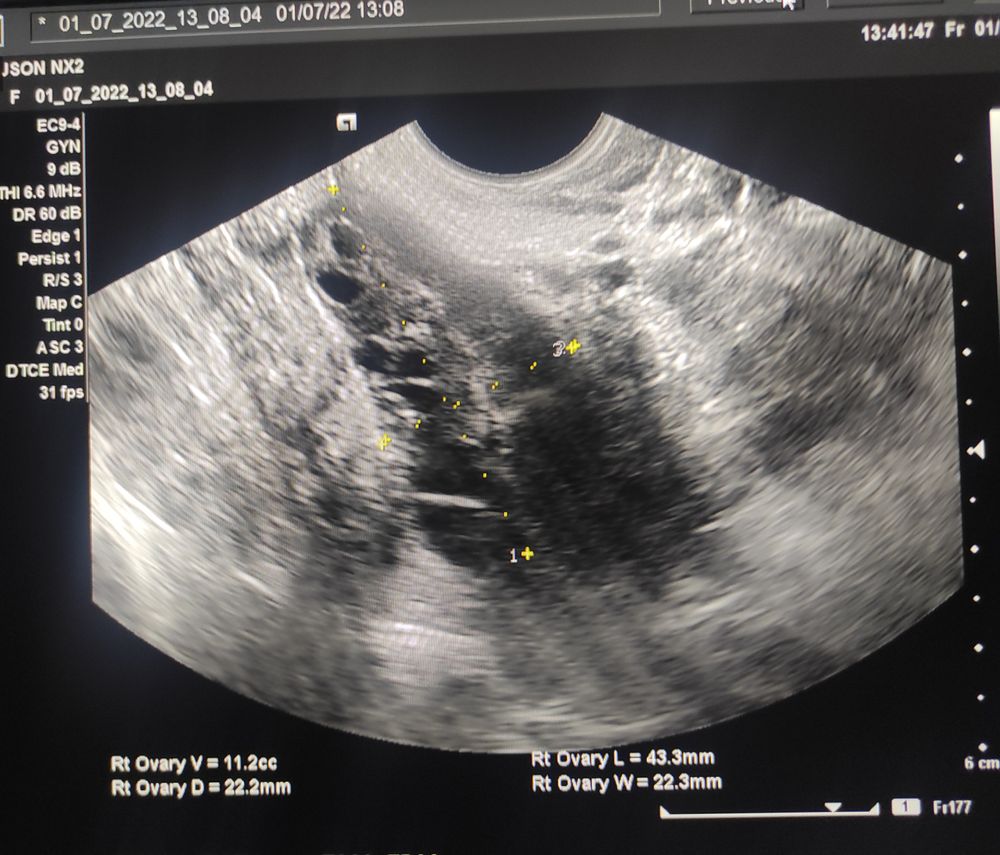

Арина С, с 1 и 2 не делали фото, 3 УЗИ сегодня своими глазами видела фолликул. 4 УЗИ сегодня вот фото, это где не увидели ничего

Каролина В, я и имела в виду 3 и 4 узи) а с 3 нет фото? Я просто хотела посмотреть на форму дф и насколько ровные края.

Арина С, к сожалению, нет ( но он был неровный. 22.2 на 21.1. но был